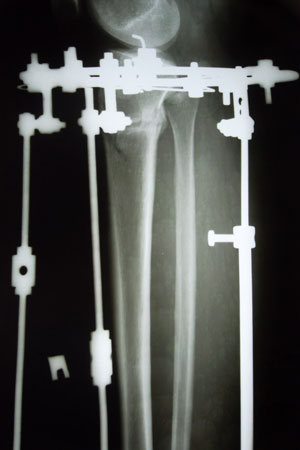

Рентген в 2 месяца с момента операции.

Вложения

SAM_8978.JPG

SAM_8980.JPG